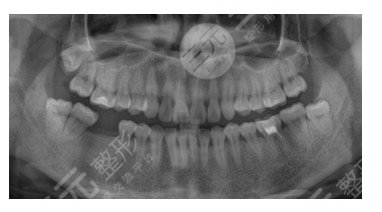

深圳友睦齿科种植牙案例

今天预约了种植牙一期,一大早就醒了。考虑到种植牙后不好吃,我做了馄饨。然后,我走了我已经知道的路线,提前十分钟到达深圳友睦齿科。先拍了CT,然后根据片子说了计划,和谈了另外还有两种牙冠。支付费用,手术和骨粉。支付费用后,测量血压并服药。因为我的手术时间比较长,让后面的一个女生先去。

缝线结很紧,比拔牙多一根线。缝纫之后,手术终于结束了!我又做了一次电脑断层扫描,术后不用挂盐水。然后,当费用结时,花费比预期的要少。从深圳友睦齿科回家后,冰敷一直留着脸的脸颊,两三个冰袋交替使用。晚饭后,煮了瘦肉粥。这时候吞咽没有问题,因为有隐隐的疼痛,饭后吃药的时候也吃了止痛药。第二天醒来,觉得脸颊浮肿。